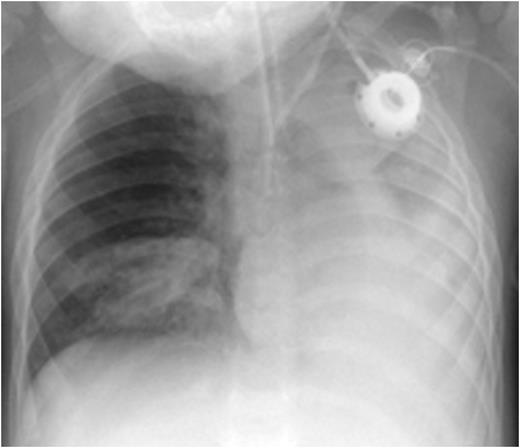

CXR before administration of plasminogen showed atelectasis of the left lung and of the right lower lobe (left panel). Six weeks after initiation of regulalar plasminogen substitution ventilation in both lungs had improved significantly (right panel)

At 2 months of age he suffered a severe respiratory syncytial virus (RSV) infection requiring ventilatory support for 5 days and a 1 month hospitalization. From this time he had recurrent respiratory problems. From 4 months of age he was treated with fresh frozen plasma (FFP) 20 mL/kg/week. At 18 months of age he was found to have exophytic lesions within both the right and left main bronchi. He had one incident of acute severe dyspnea with cyanosis which responded to non- invasive oxygen insufflation. Subsequently he had repeated bronchoscopies with laser removal of bronchial lesions with FFP cover. At 20 months of age during preparation for bronchoscopy he had an episode of acute cyanosis and cardiac arrest with asystole and was resuscitated after 30 minutes. CXR showed atelectasis of the left lung and of the right lower lobe. He was admitted to the ICU and required both ventilatory and circulatory support. Profuse viscous lung secretions were aspirated.